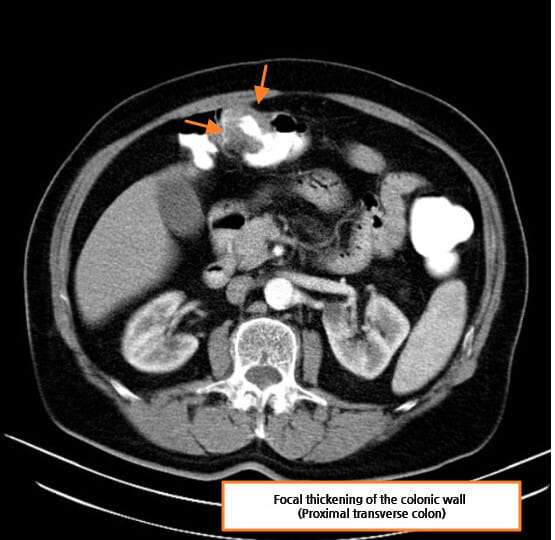

CT 소견 (Contrast-enhanced CT)

🔵 장벽 비후 (Bowel wall thickening)

암 부위의 장벽이 국소적으로 두꺼워지며, 조영증강되는 불균일한 덩어리로 관찰됩니다.

🔵 주위 지방 침윤

장 주변 지방조직에 염증 또는 종양 침윤이 퍼지며 음영이 흐려지는 소견입니다.

Di Muzio B, Colon adenocarcinoma. Case study, Radiopaedia.org (Accessed on 15 Jul 2025) https://doi.org/10.53347/rID-15157

Niknejad M, Colon cancer. Case study, Radiopaedia.org (Accessed on 15 Jul 2025) https://doi.org/10.53347/rID-87193